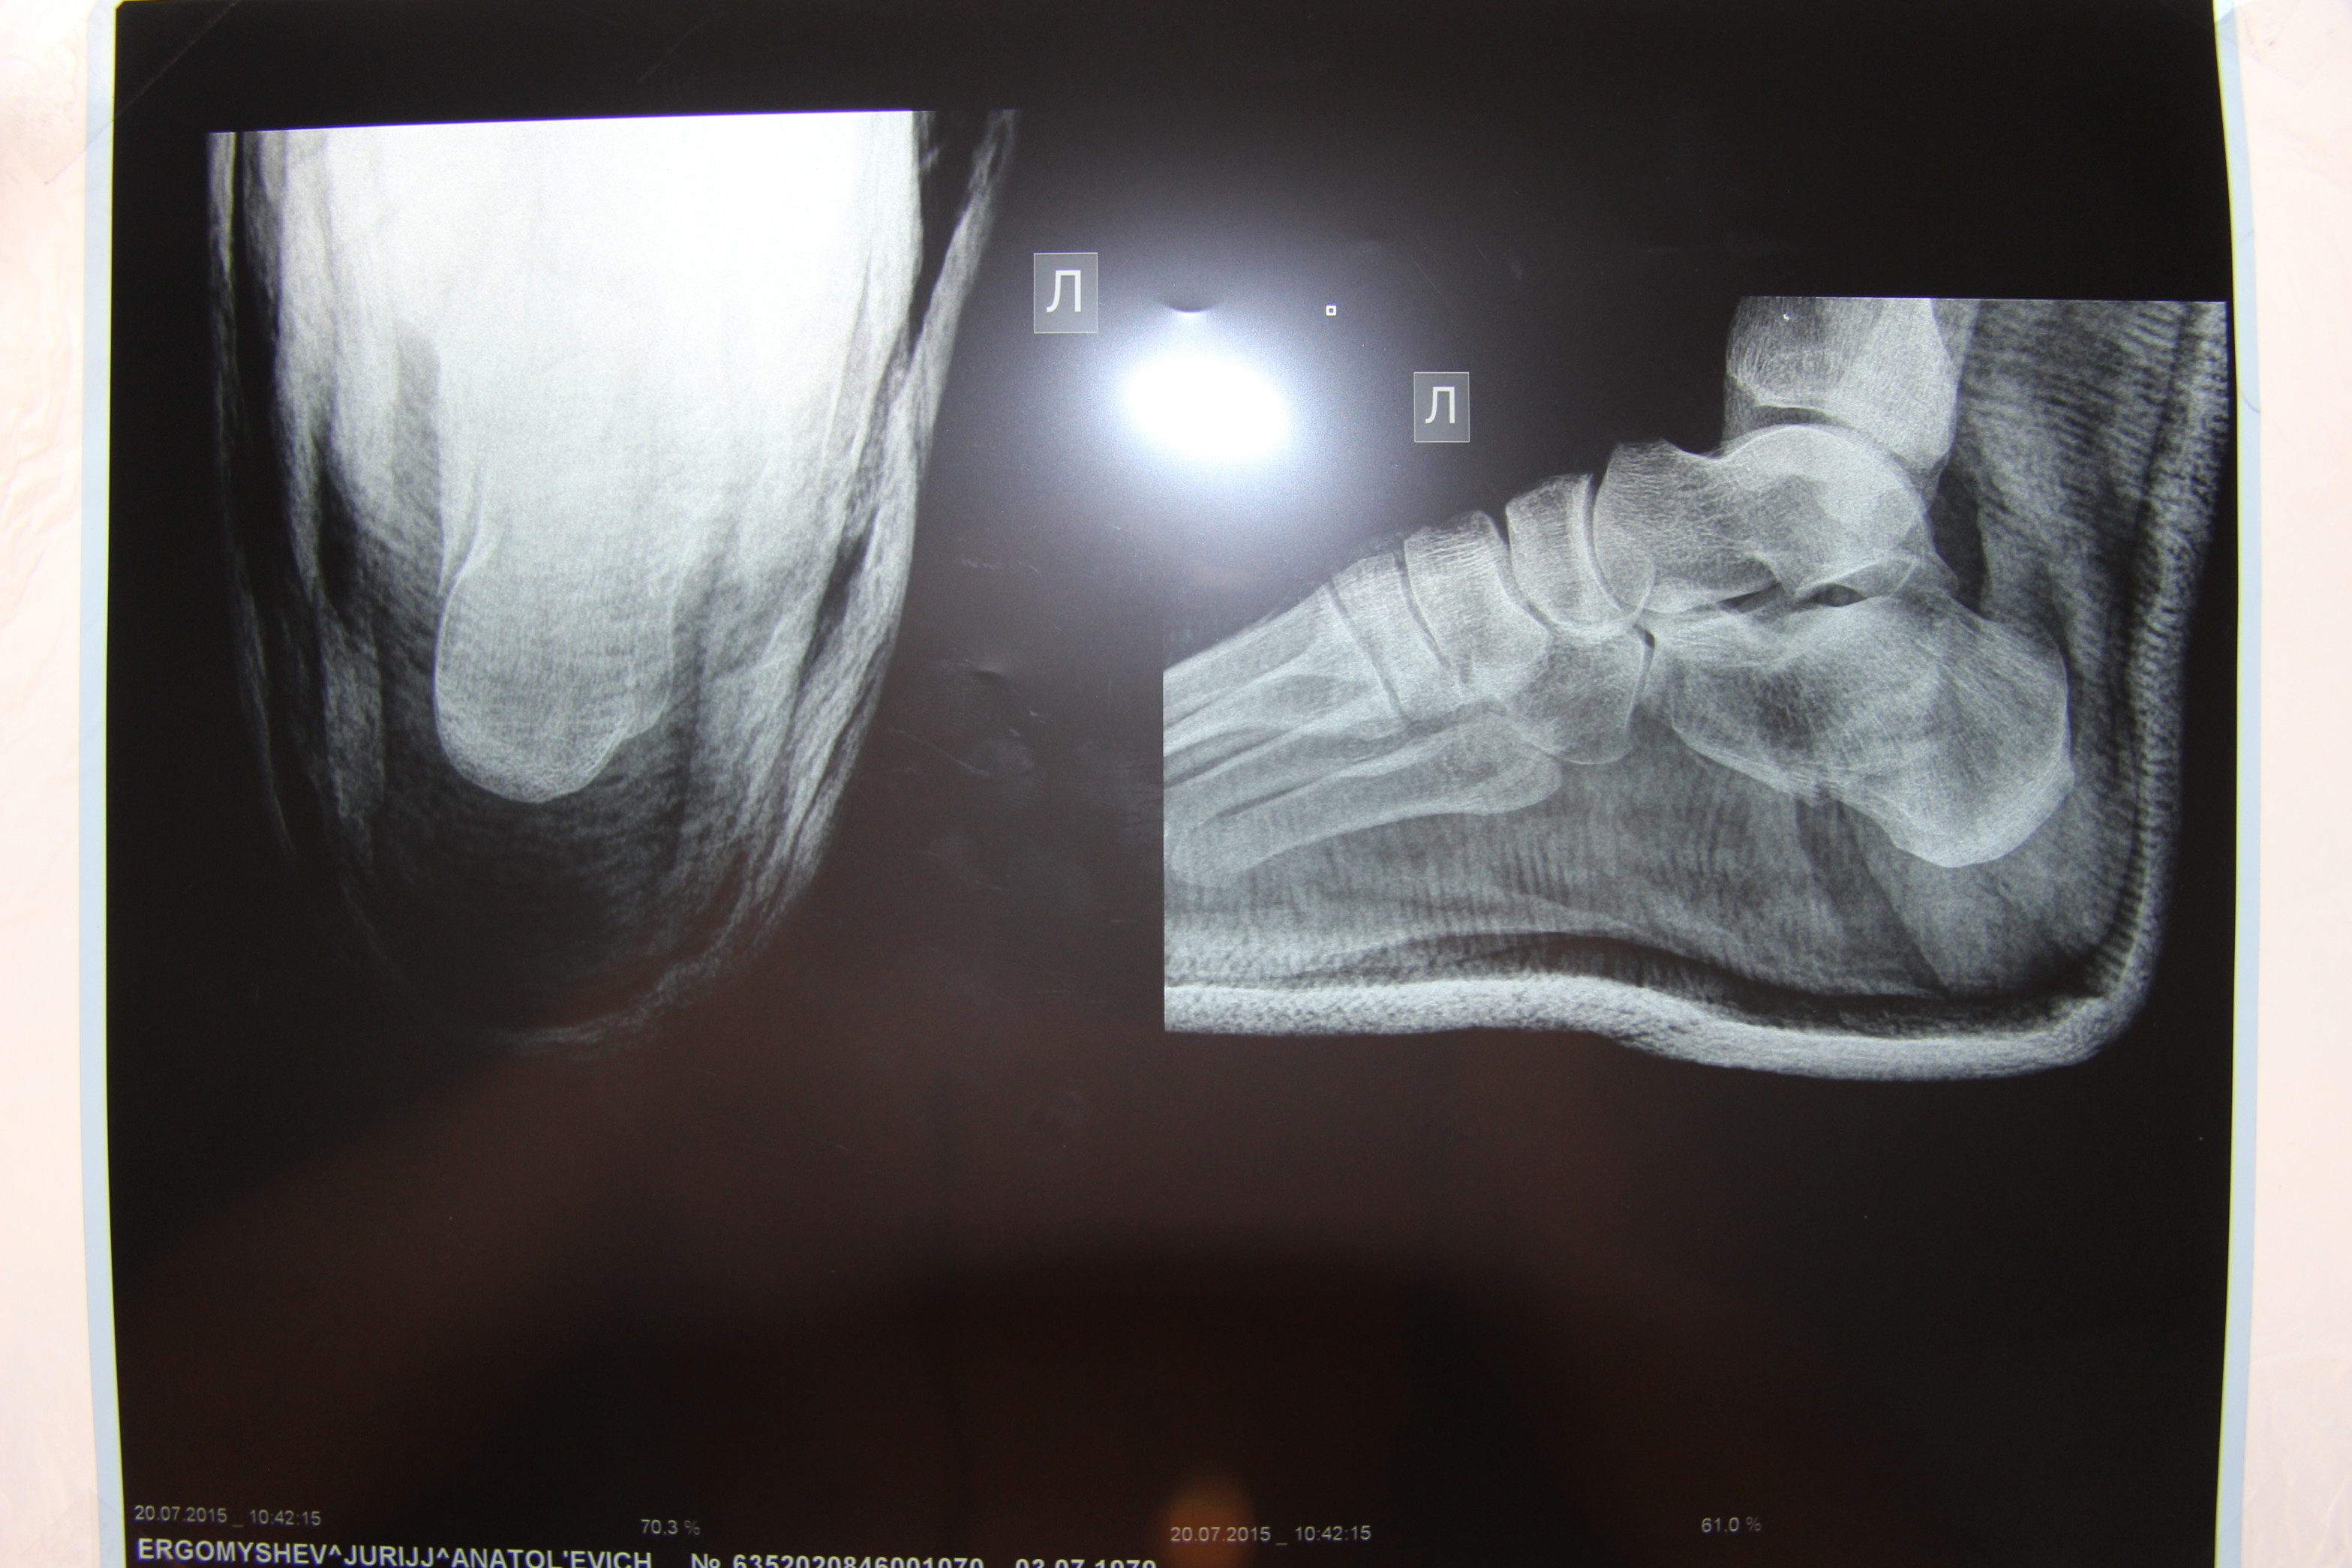

Здравствуйте! Уважаемые доктора, посмотрите пожалуйста снимок перелома пяточной кости, что можете сказать. Серьезный ли там перелом?Мнения у врачей расходятся, кто говорит нужна операция, кто говорит сама срастется. Ни операции, не гипс не наложили, очень переживаем. Спасибо!

Здравствуйте. На представленных рентгенограммах-достаточно тяжелый перелом пяточной кости. К счастью суставная поверхность пяточной кости, участвующая в формировании подтаранного сустава интактна, по крайней мере рентгенологически. Если перелом консолидируется в таком положении, то вероятнее всего будет ограничение подошвенного сгибания и болевой синдром при ходьбе. Чем меньше времени прошло после травмы, тем больше вероятность выполнить данное вмешательство малоинвазивно.